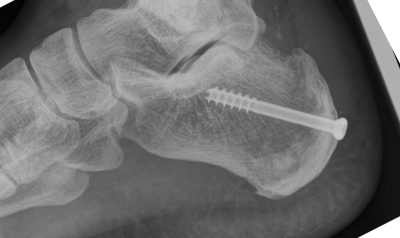

Alles aufgeräumt, Exostose entfernt und einen Keil aus dem Fersenbein herrausgesägt und die Ferse angeklappt und verschraubt. Der Sehnenansatz bleibt unverändert.

In den Bildern sieht man ganz gut wie der obere Teil des Fersenbeins durch das Anklappen kürzer ist.